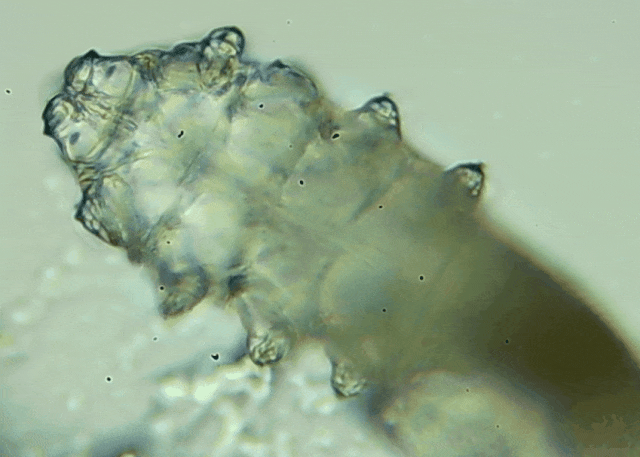

我只是眼睛癢,結(jié)果醫(yī)生說(shuō)我睫毛里有80只蟲(chóng)?這不是恐怖片,而是真實(shí)的病例:武漢一13歲男孩,右眼9根睫毛里檢出39只螨蟲(chóng),左眼9根里檢出47只。 而且這不是極端個(gè)案,廈門(mén)眼科中...

眼瞼位于眼球前面,分為上下眼瞼,而睫毛、一些腺體的開(kāi)口和淚小點(diǎn)都在眼瞼邊緣,也就是瞼緣上。蠕形螨是一種寄生于毛孔、腺管和瞼緣上的螨蟲(chóng),因?yàn)轶w型微小,肉眼無(wú)法察覺(jué)。...[詳細(xì)]